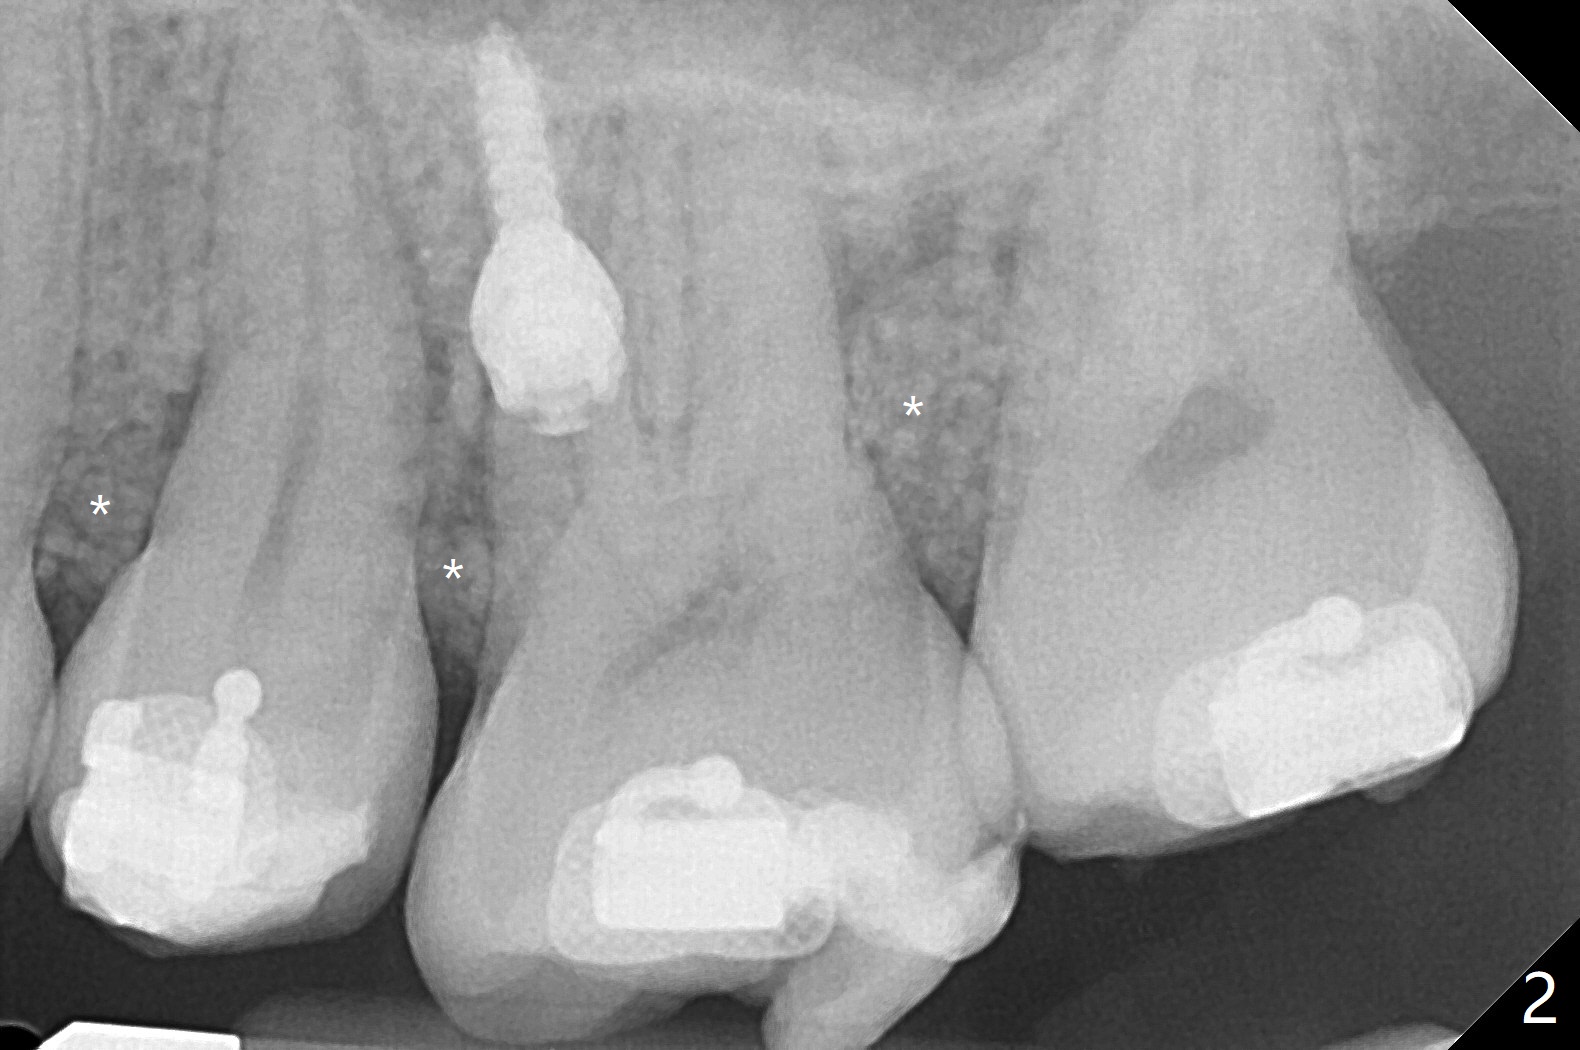

前几周介绍一个矫正砸锅病例,微型植体植入左上6(for intrusion,矫正压低)颊侧远中没有骨质区域,造成局部骨质缺损(图一:>)。颊侧,腭侧牙龈沟切口,翻瓣,清创后,植入粘性骨粉(图二:*,也在颊侧,腭侧植骨),覆盖PRF膜,使用4-0 Monoglyc缝线缝合。对于左下6缺失,原先病人(31岁女)要求前移7,8,初步矫正(2个月内)引起7松动(图三),经过讨论,病人同意拔除8,然后竖直7。拔出后,放置半块胶原塞(控制出血,图四:C),然后植骨(*),最后放置另外半块胶原塞(C),4-0 PGA缝合。术后一个月腭侧放置power chain压低磨牙(图五)。术后2.5个月缺牙间隙大于前磨牙,可以种植,同时7近中植骨(图六:*(粘性骨粉))。整合后利用6作为抛锚继续做7竖直。